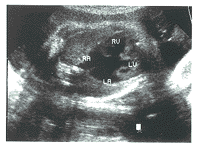

先心病组TR均有心内结构异常。其中:肺动脉狭窄3例,表现肺动脉瓣环或内径缩小,右房显著扩大,右室壁肥厚(图1)。左心发育不良综合征2例,表现左心房、室缩小,主动脉缩小,右心房、室及三尖瓣环扩大(图2)。完全型心内膜垫缺损1例,表现房间隔及室间隔上部缺失,心腔相互交通,房室瓣发育异常,形成左右心室共同房室瓣(图3)。

四腔观:右房扩大,右室肥厚

图1 肺动脉狭窄